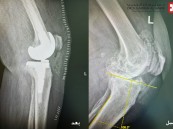

مستشفى الحبيب بالخبر يُجري عملية زراعة مفصل معقدة لإعادة قدرة المشي لثمانينية

نجح مستشفى الدكتور سليمان الحبيب بالخبر، وعبر تقنية الروبوت الجراحي "Robotic Surgery"، في إنهاء معاناة مراجعة تبلغ من العمر 84 سنة، كانت تشكو من ألم حاد ومزمن في مفصل الركبة اليسرى، أفقدها القدرة على المشي. ذكر ذلك الدكتور محمد سكيك ...